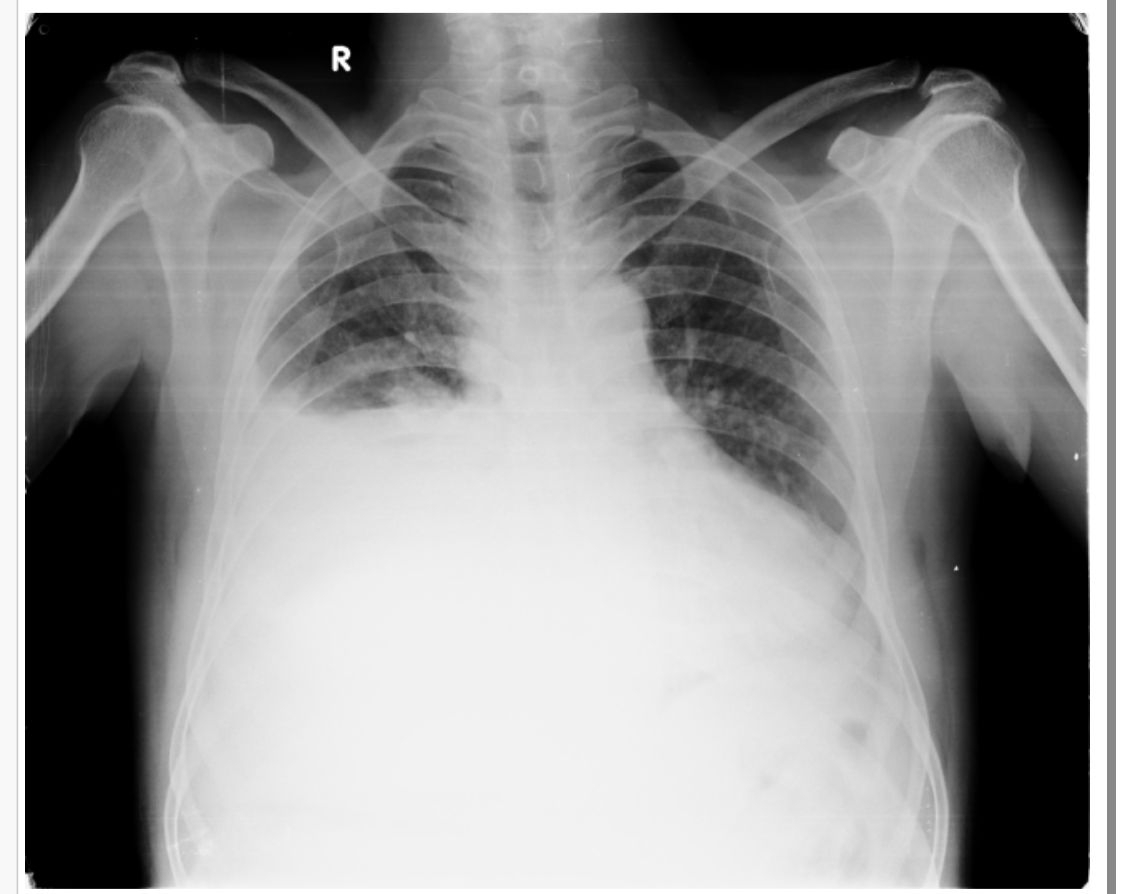

A 51 year old male with Right sided plueral effusiin

Right sided Pleural effusion likely infectious etiology.

XRAY:CURVED SHADOW AT THE LUNG BASE ,BLUNTIJG THE COSTOPHRENIC ANGLE AND ASCENDING TOWARDS THE AXILLA

Interpretation: Exudative pleural effusion.

1.right sided pleural effusion